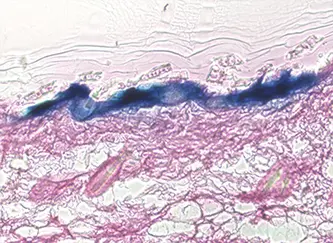

LacZ遺伝子をコードしたプラスミドDNAによるβ-ガラクトシダーゼの発現(青色染色領域が発現部位)